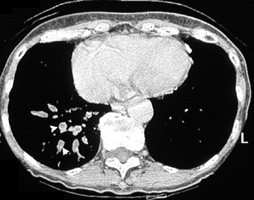

Bronchiectasis

Dilated bronchi with peribronchial fibrosis, visualized in various cuts of CT as cystic spaces, tubular shadows and branching densities.